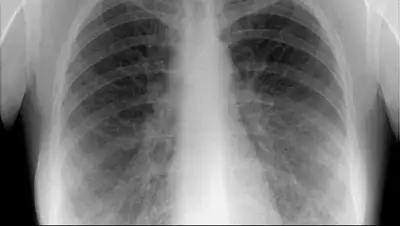

Сегодня с самого утра в нашу редакцию звонят взволнованные родители столичных школьников, сообщает Седьмой канал. Люди напуганы слухами о, якобы, участившихся случаях заболевания туберкулеза среди детей. Говорят, в учебных заведениях массово вакцинируют учеников, и активно информируют о последствиях этого недуга. Стало известно и о новом факте заболевания третьеклассника в Астане.

Медсестра этой столичной школы проверяет результаты пробы манту. Несколько дней назад детям ввели подкожно туберкулин. Говорит, что процедура плановая. Только в последнее время все больше положительных результатов. Это значит, что дети находятся в группе риска. Под особым контролем ученики 4 класса. Именно там произошел случай заболевания туберкулезом. Школьник сейчас получает лечение.

Еще один случай заболевания туберкулезом зафиксирован уже в 2015 году у третьеклассника восьмой школы Астаны. Об этом сообщают в столичном тубдиспансере. По спискам, которые имеются здесь, на лечении сейчас находятся 22 ребенка. Из них 13 - ученики столичных школ. По анализу специалистов, почти все поступившие дети переехали в Астану из других регионов страны.

По словам врачей, туберкулез - болезнь коварная, протекающая, как правило, без клинических симптомов. Медики призывают родителей еще в роддоме вакцинировать своих детей и не отказываться от пробы манту. Говорят, недуг может напасть на любого, независимо от социального статуса.